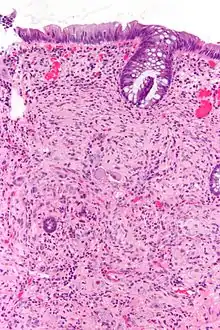

Pathologically, ganglioneuromas are composed of ganglion cells, Schwann cells and fibrous tissue.[5] Ganglioneuromas are solid, firm tumours that typically are white when seen with the naked eye.